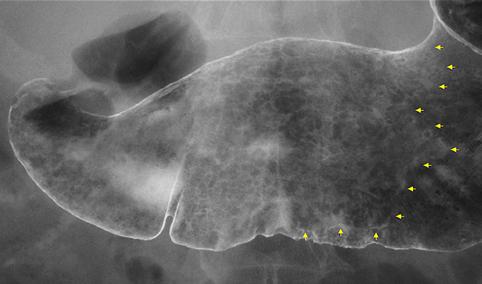

질환(병리주체)의 분류 악성 상피성종양/선암

부위(장기별) 위(부위)/2개 이상

검사방법 X-P

종양의 육안분류 0형(표재형)/IIb형(IIb+IIc)

종양의 최대경(밀리미터) 40이상

종양의 심달도 m